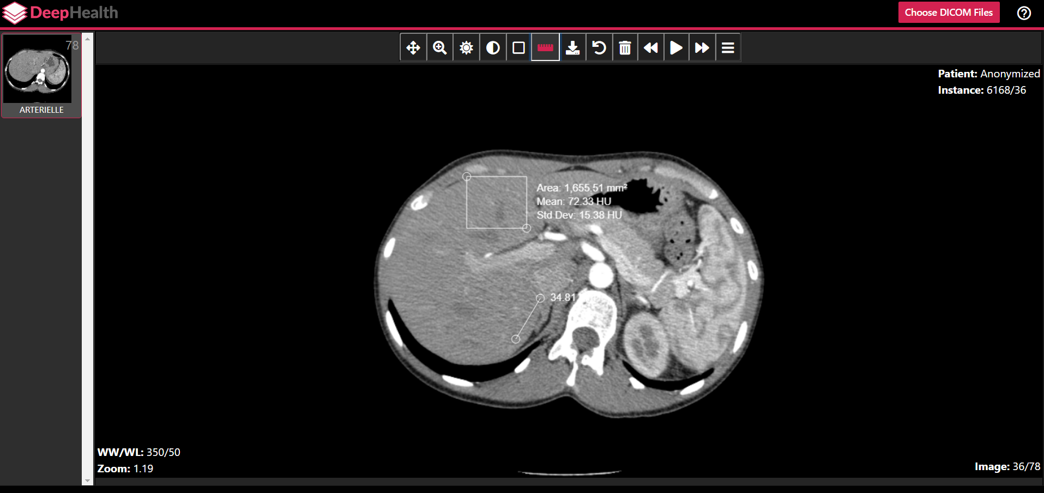

Algorithmic Research at UMass Boston

AI Implementation at UMass Memorial

Intelligent Annotations

Haehn et al., CVPR 2018

post-training optimization of GP acc.

from 0.5982 to 0.9087

Preliminary Results